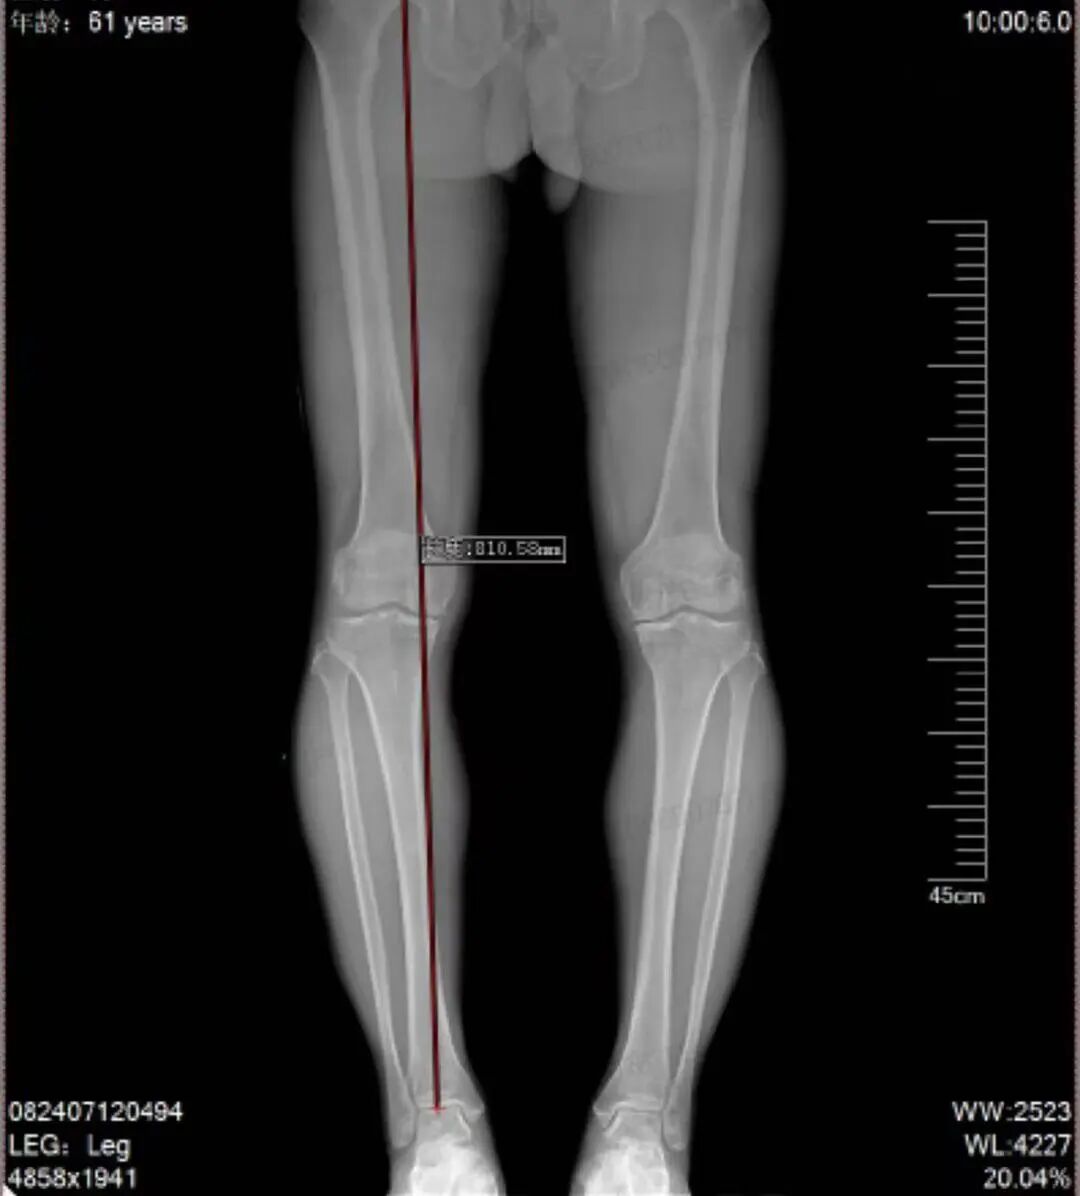

在苏州京东方医院骨一科,王磊主任为他找到了症结:膝关节骨关节炎。影像检查显示,李先生因「O 型腿」导致 下肢力线异常,身体重量长期过度压在其右膝内侧,造成了软骨的严重磨损。磨损与畸形相互加剧,陷入恶性循环。

王磊主任解释,HTO 手术的原理类似于「矫正一棵长歪的树」。它并非替换关节,而是通过精确调整胫骨上端的角度,将膝关节的承重主力线,从已磨损严重的内侧区域,转移至相对健康的外侧软骨区。